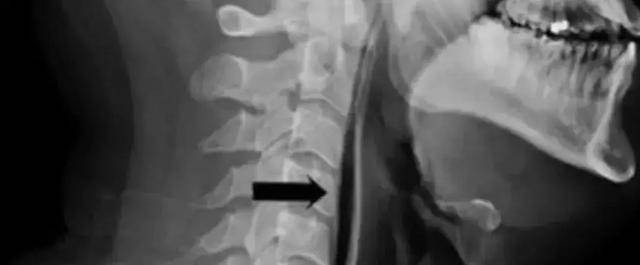

Bóng được chỉ định bởi mũi tên màu đen là không khí xâm nhập vào mô mềm của cổ

Sau khi kiểm tra X quang, bác sĩ còn phát hiện không khí rò rỉ từ khí quản của người đàn ông thông qua chỗ bị vỡ và đi vào mô mềm của cổ. Nguyên nhân dẫn đến việc này chính là do hành động nhịn hắt hơi, khiến cổ, khí quản bị vỡ.